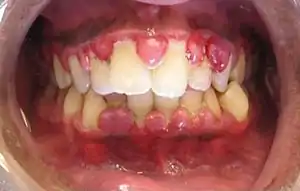

| Gingival enlargement can be a feature in some periodontal diseases. | |